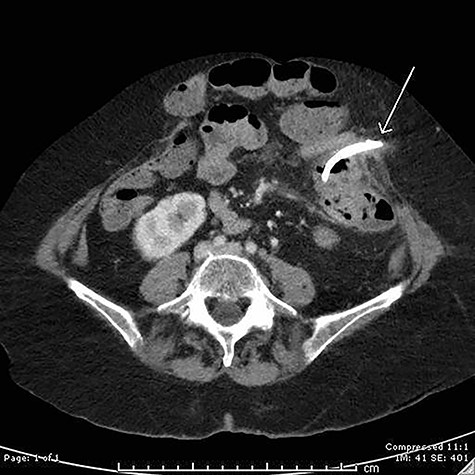

On examination, she had a large midline laparotomy scar, large reducible incisional hernia with localized peritonism in the left lower quadrant. She did not have generalized peritonitis. Biochemistry included a mild neutrophilia of 10.0 × 109/l (reference range 2.0–8.0 × 109/l), lactate of 2.6 mmol/l (reference range: 0.5–2.2 mmol/l) and C-reactive protein (CRP) of 125 mg/l (reference range < 2.0 mg/l). Cross-sectional imaging demonstrated a contained perforation around the migrated biliary stent within the incisional hernia (see Figs 1 and 2).

Axial computed tomography (CT) image demonstrating perforation of a migrated biliary stent into the anterior abdominal wall.